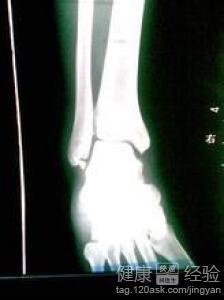

骨折手术后,身体需要大量的营养来修复受损的骨骼。这时候,选择一些既美味又营养的食物就显得尤为重要。而瓜果,正是这样的佳品。它们富含水分、维生素和矿物质,能够帮助你补充流失的水分,促进新陈代谢,加速康复。